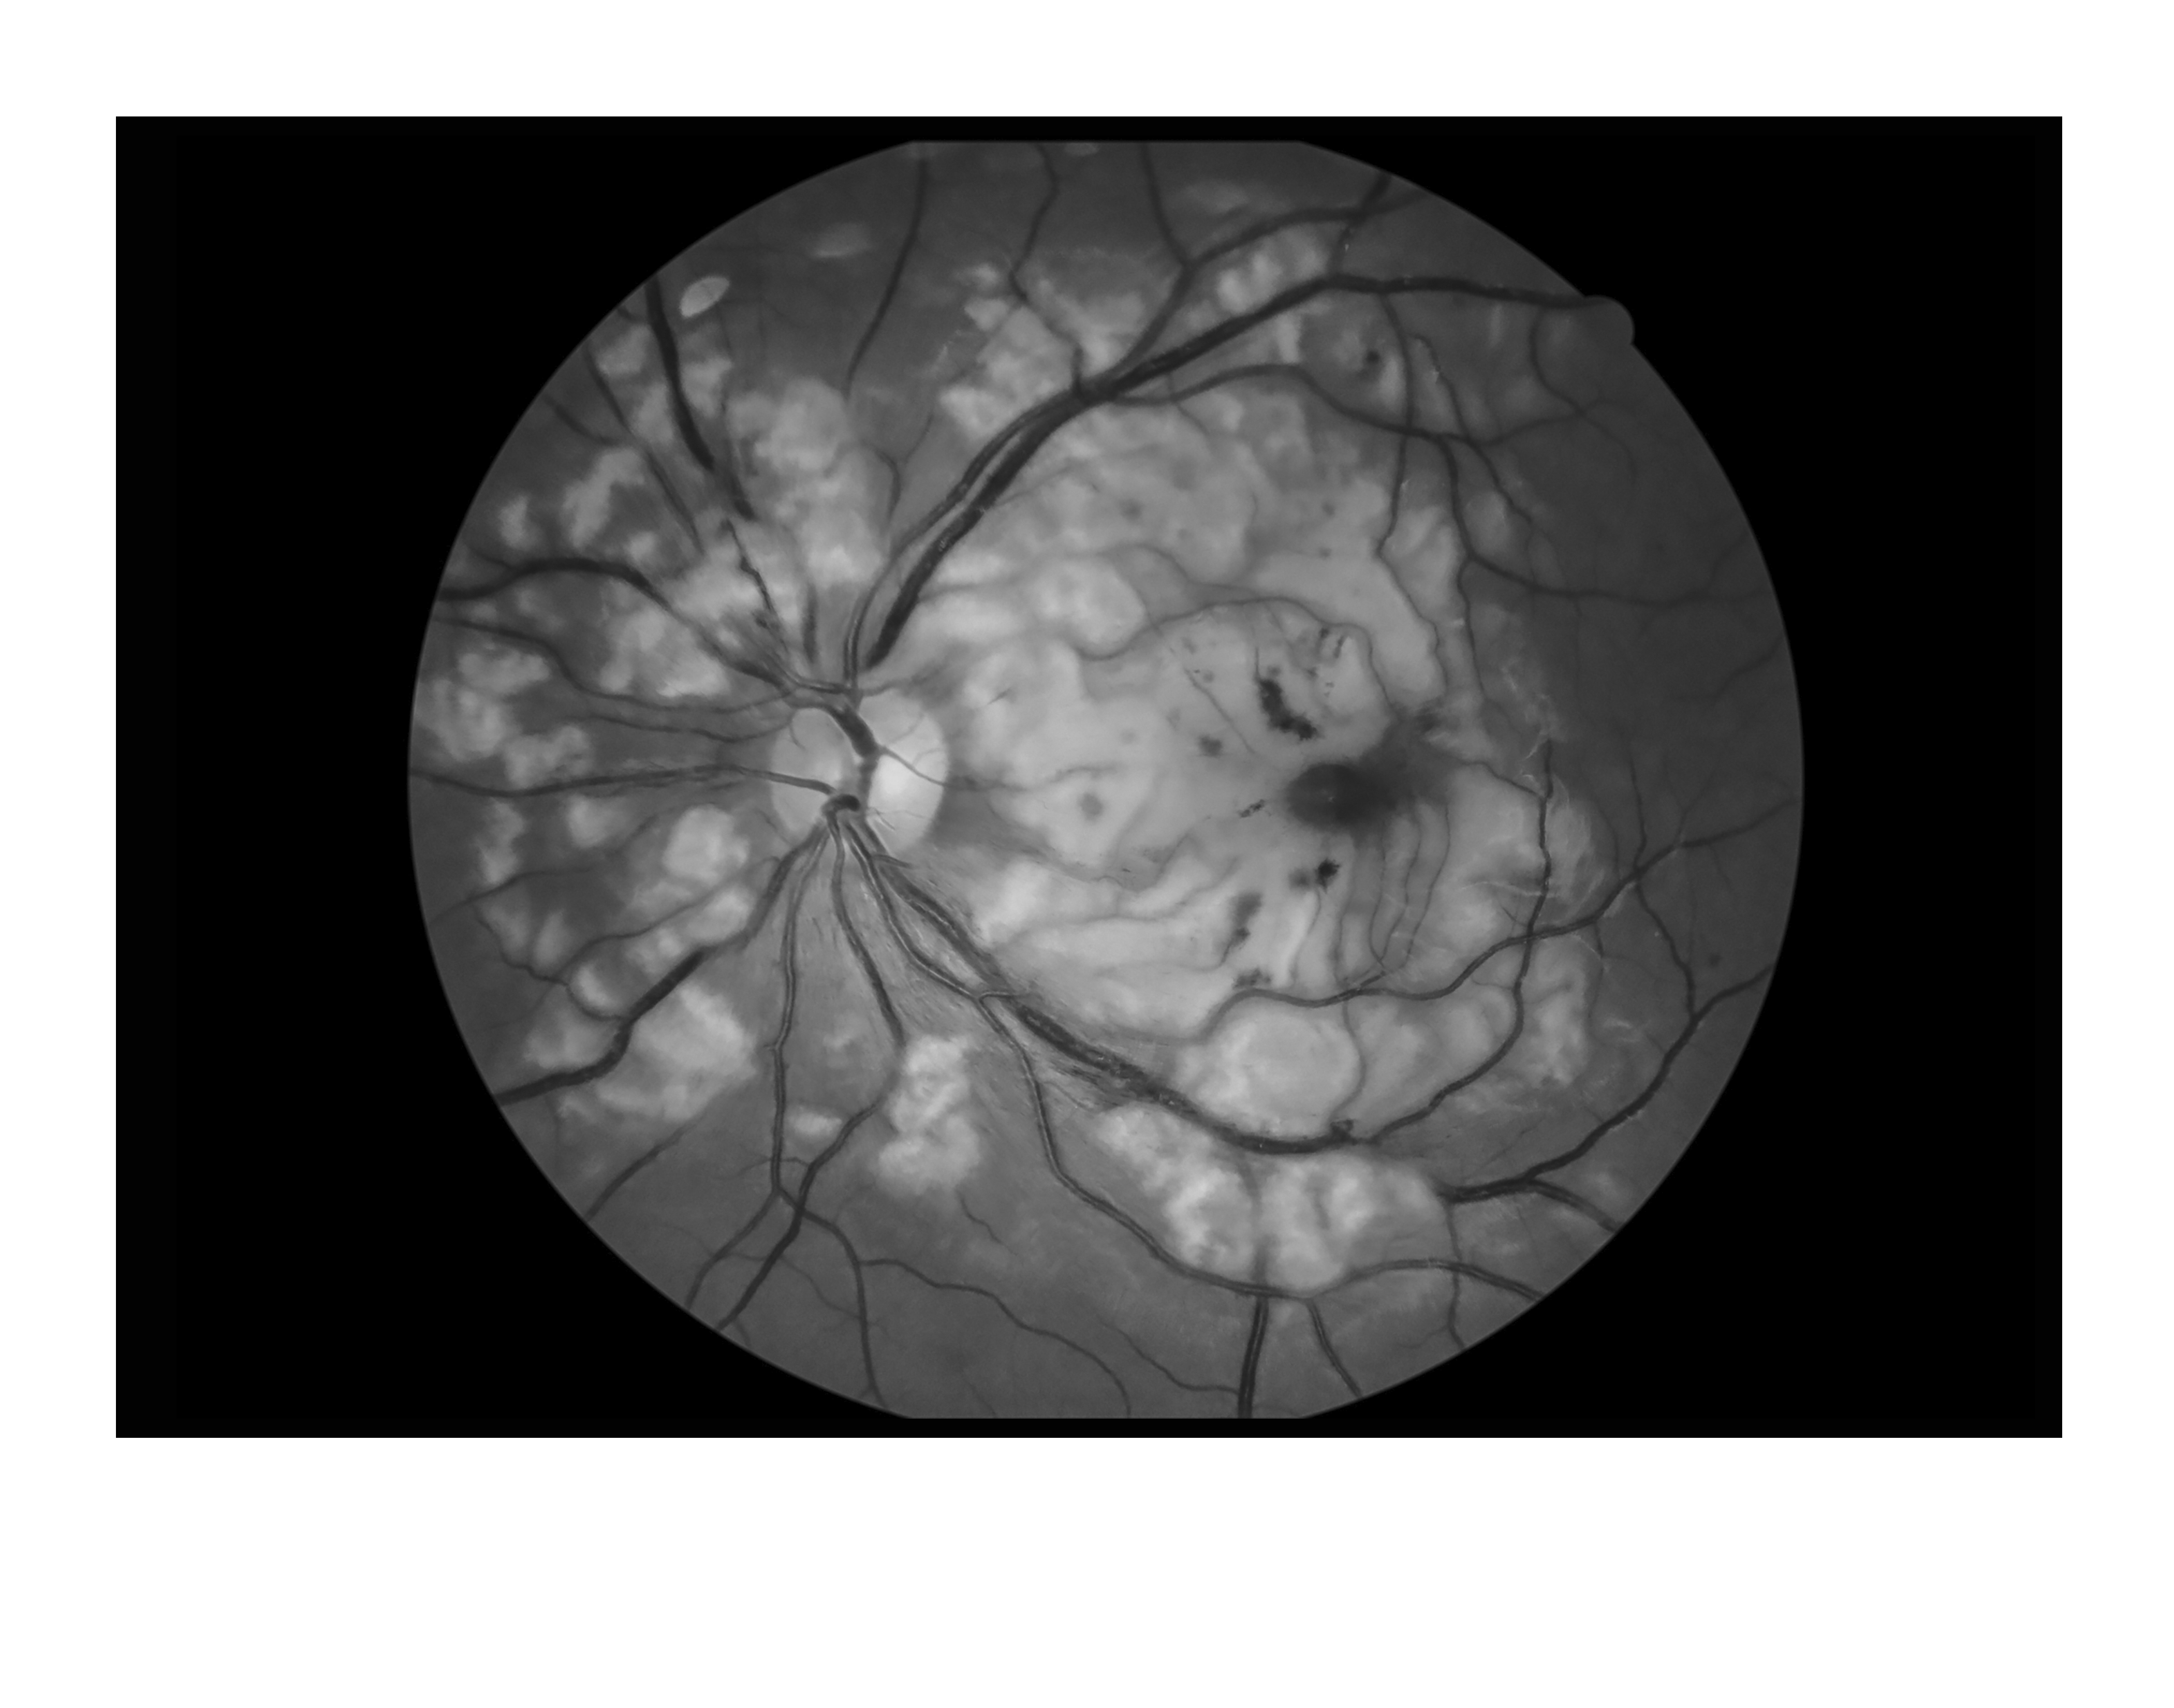

Choroidal Abnormalities in Neuro-Fibromatosis Type Presented by Barbara Klemenc This photograph received Third Place in the category "Monochromatic Photography" and was displayed in the 2024 OPS Exhibit. Filed Under Retina OPS Photo